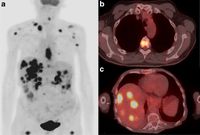

Nuclear medicine uses radioactive substances, called radiopharmaceuticals, in the diagnosis and treatment of a range of diseases. These substances are chosen or especially developed to be taken up predominantly by one organ or one type of cell in the body. Nuclear medicine offers unique diagnostic information in oncology, cardiology, endocrinology, neurology, nephrology, urology and other areas. Such information is not obtainable, or obtainable only with less accuracy, by other modalities. For nuclear medicine diagnostic procedures, trace amounts of radiopharmaceuticals are administered to patients through injection into veins (intravenous), skin (intradermal) or tissues (intraparenchymal) as well as breathing in (inhalation) or eating/drinking (ingestion). After intake, the function, or physiology, of various tissues, organs or organ systems can be demonstrated. For example, in cancer patients, nuclear medicine imaging can be used for diagnosis (i.e. is a cancer present), staging (i.e. how far has it spread), assessment of response to therapy or of possible disease recurrence. Nuclear medicine cameras are now commonly combined with a CT unit (e.g. hybrid SPECT/CT and PET/CT) which allows precise anatomic localisation of pathology.